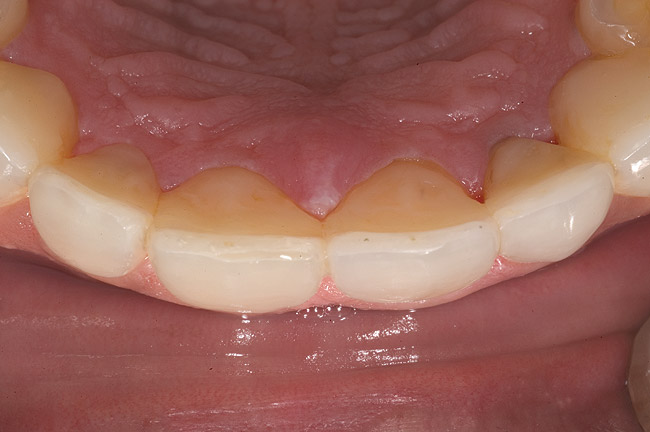

Figure 15  Maximum intercuspation (MIP) after restoration of the lost palatal anatomy.

Figure 15